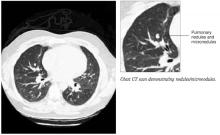

A 33-year-old African American woman came to the office with a 2-week history of skin lesions and itching. The lesions started with a single blister on her left elbow; numerous other blisters subsequently appeared on her forearm and hands. One week before this visit, she had been given a presumptive diagnosis of bullous impetigo and was treated with cephalexin.

Despite the antibiotics, other lesions soon appeared in the nuchal and breast folds, axillae, and scalp areas. Several had ruptured, producing purulent, malodorous material. She had no known allergies, no medical problems aside from obesity, and no significant family history or recent travels. She denied any illicit drug use and had not been on any medications.

On physical exam, 1 large bulla was seen on the fourth digit of her left hand (Figure 1). The patient was obese, and inspection of the skin folds of her abdomen showed multiple suppurative lesions and erosions where previous bullae were found (Figure 2). No oral or gingival erosions were seen. Labs showed a white blood cell (WBC) count of 10.5 x109L], hemoglobin of 11.0 g/dL, and hemoglobin A1cof 5.5; liver function tests were normal. Gram stain showed no WBC and had rare Gram-positive bacilli. Potassium hydroxide prep of a skin lesion scraping showed no fungal elements. A herpes culture was performed along with a punch biopsy.

FIGURE 1

Bulla on the index finger

Left index finger bulla, which appeared 10 days after onset of disease.

FIGURE 2

Multiple bullae on the trunk

Right breast and abdominal folds with multiple flaccid bullae and denuded areas.